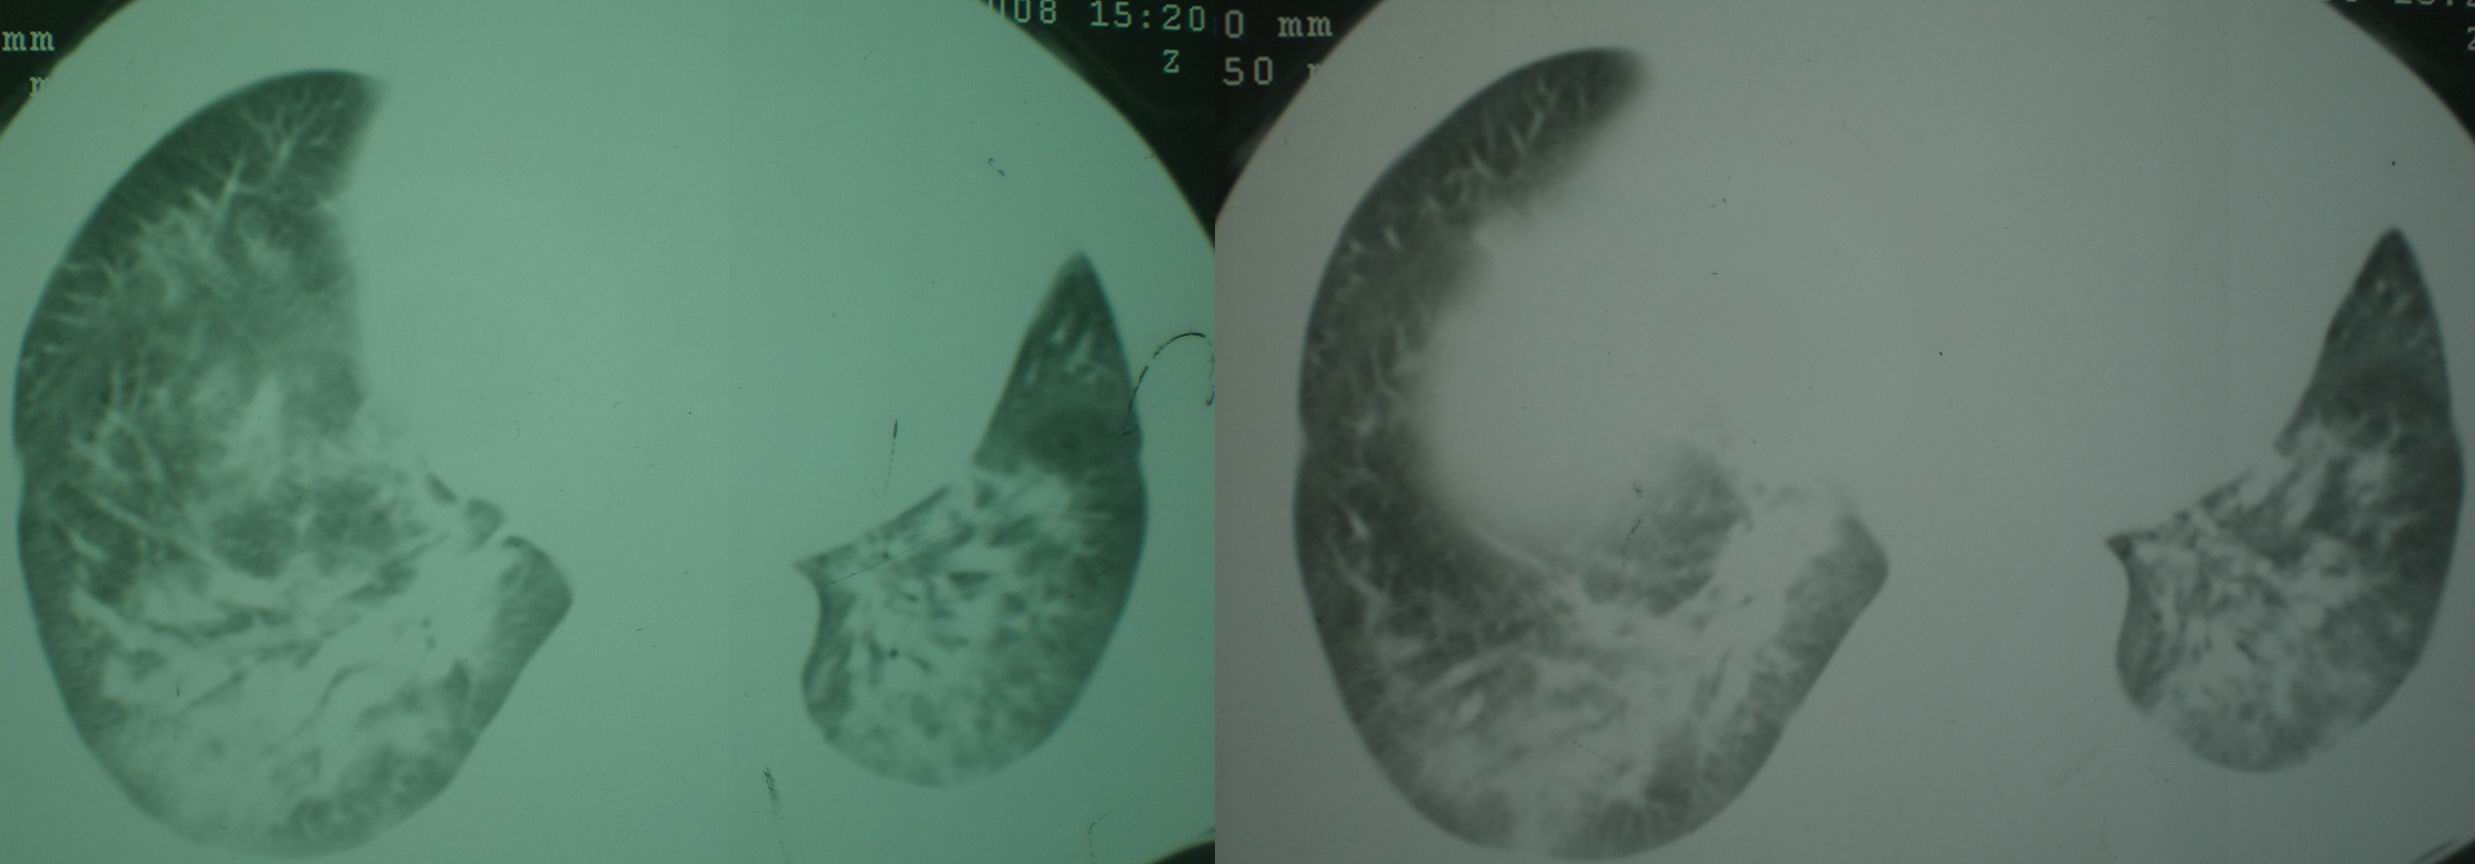

2008年9月18日ct片